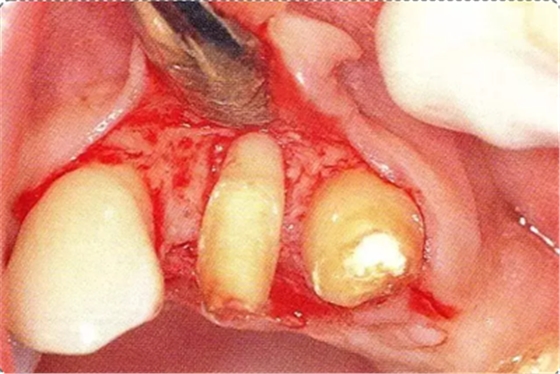

圖10-4 骨缺損部位進(jìn)行骨修整結(jié)束的狀態(tài)。